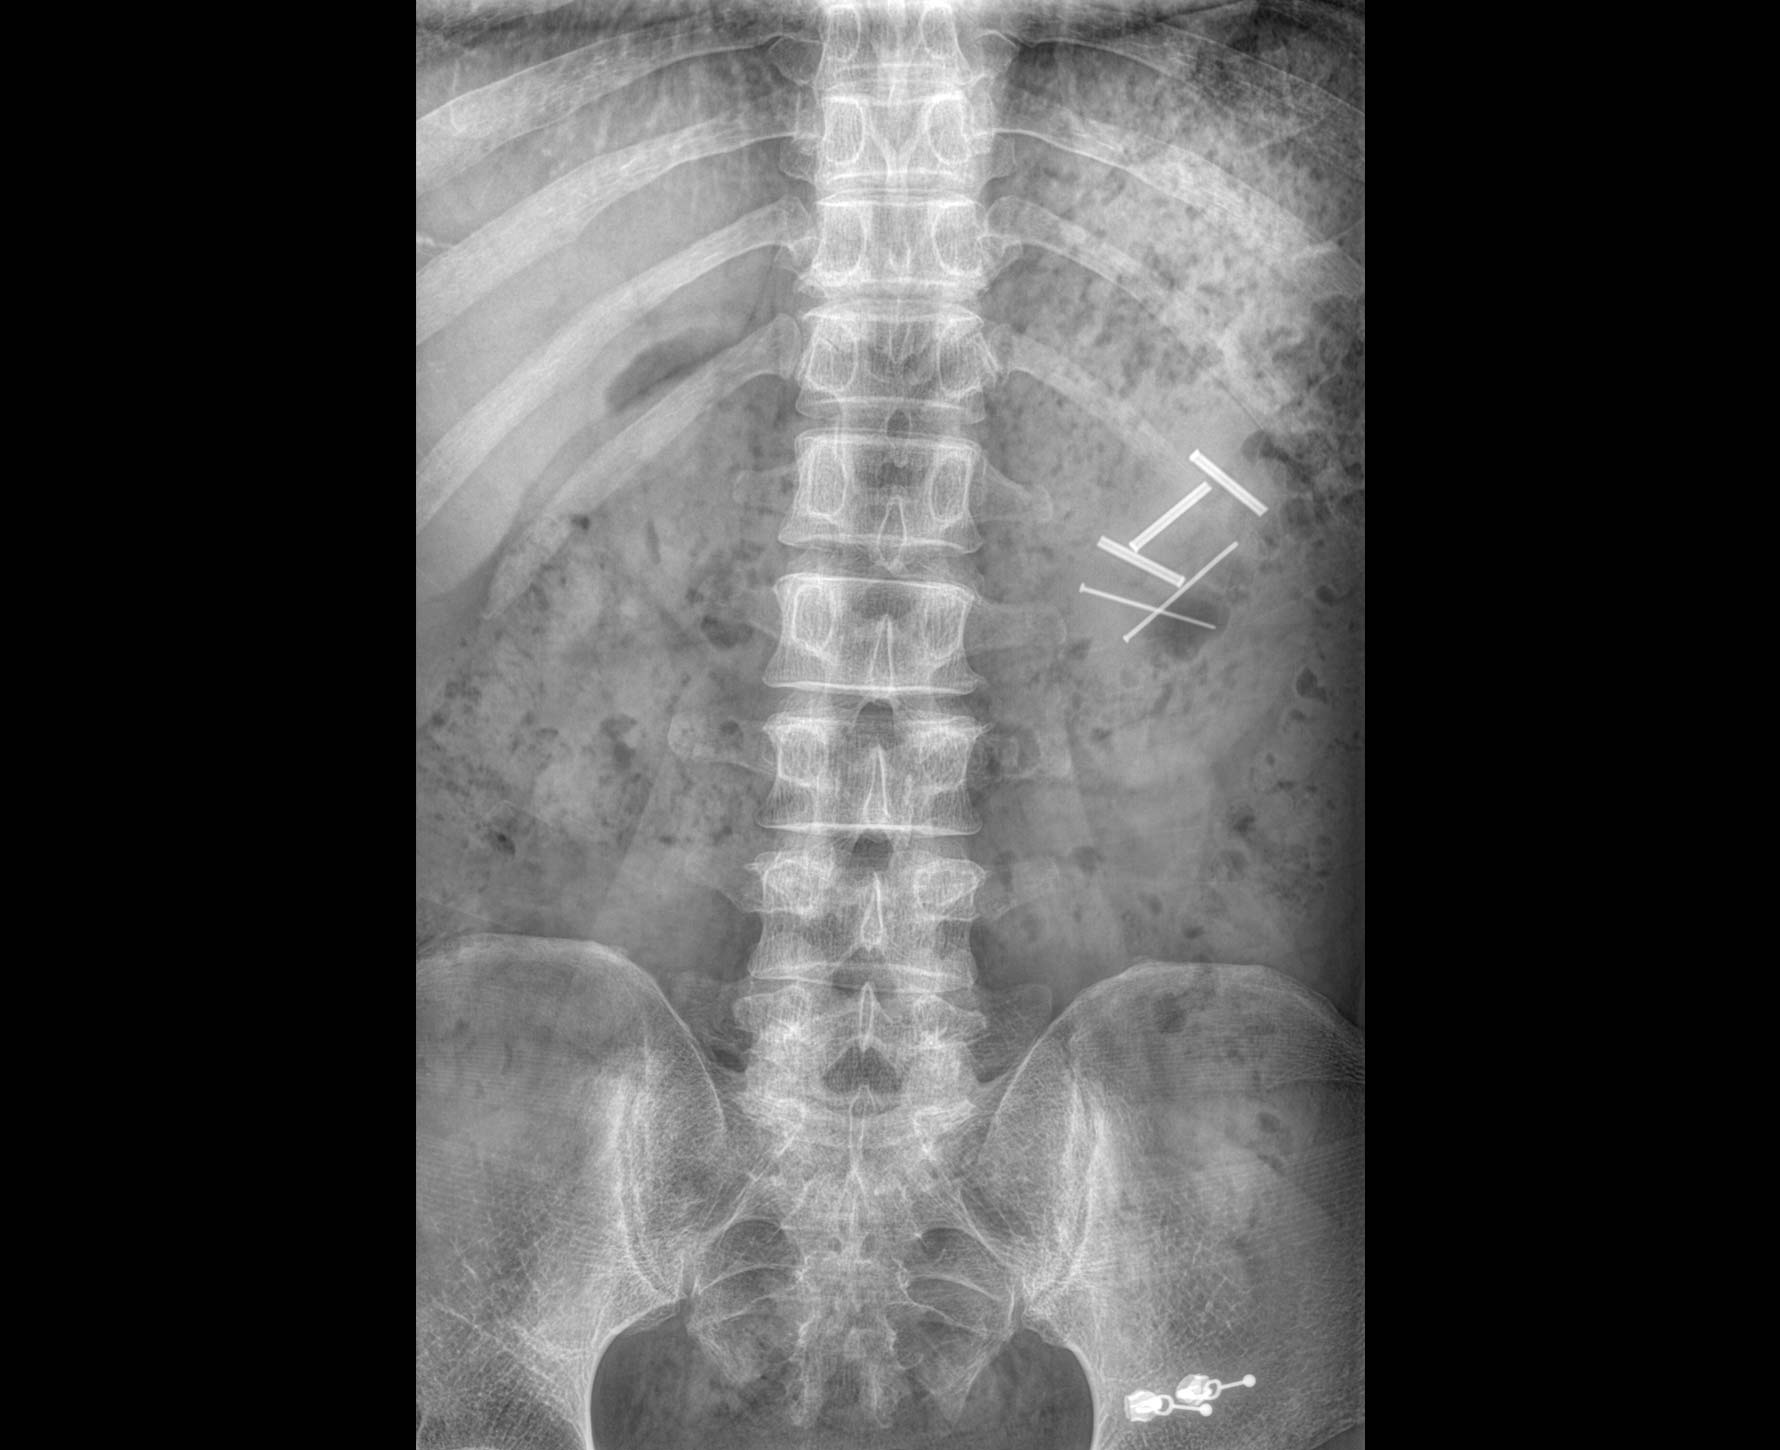

• 拍片

适用于全身各部位摄影

(常规摄影和特殊摄影)